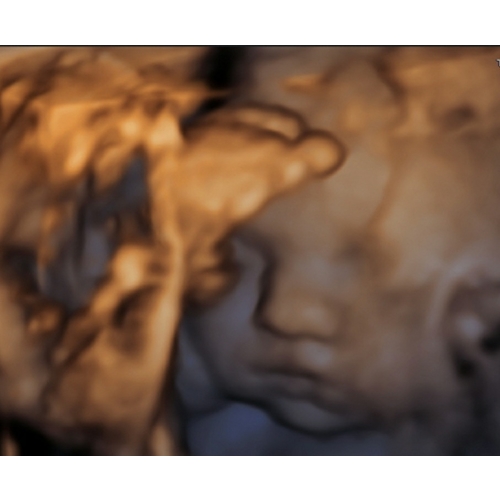

24.2

Onze dochter heeft bij elke echo dr handen voor dr gezichtje , dit was dus het beste resultaat..

Toch vind ik m prachtig! 😍 papa's indo neusje en mama's volle lippen 🥰